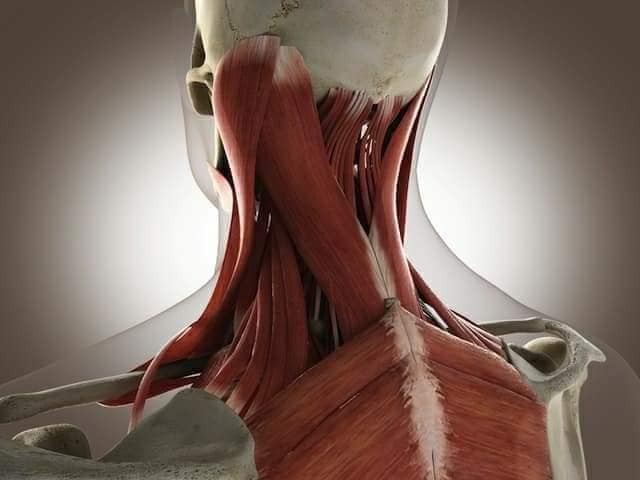

М'язова система людини є однією з основних систем організму, що відповідає за рухи, підтримання пози та стабільність. Вона складається з понад 600 м'язів, які можна класифікувати на скелетні, гладкі та серцеві м'язи. Скелетні м'язи, які є об'єктом нашого детального розгляду, дозволяють контролювати навколишній світ і виконувати різноманітні рухи. Особливу увагу в нашій статті буде приділено шейним і спинним м'язам, оскільки ці групи м'язів мають критичне значення для підтримання правильного постава та функціонування хребта.

Шийні м'язи

Шийні м'язи мають важливе значення для підтримки голови і забезпечення її рухів.

М'язи задньої групи

М'язи, що розширюють шию: М'язи, що розширюють шию: включають трапецієподібний м'яз, який бере участь у піднятті плечей і розширенні шиї.